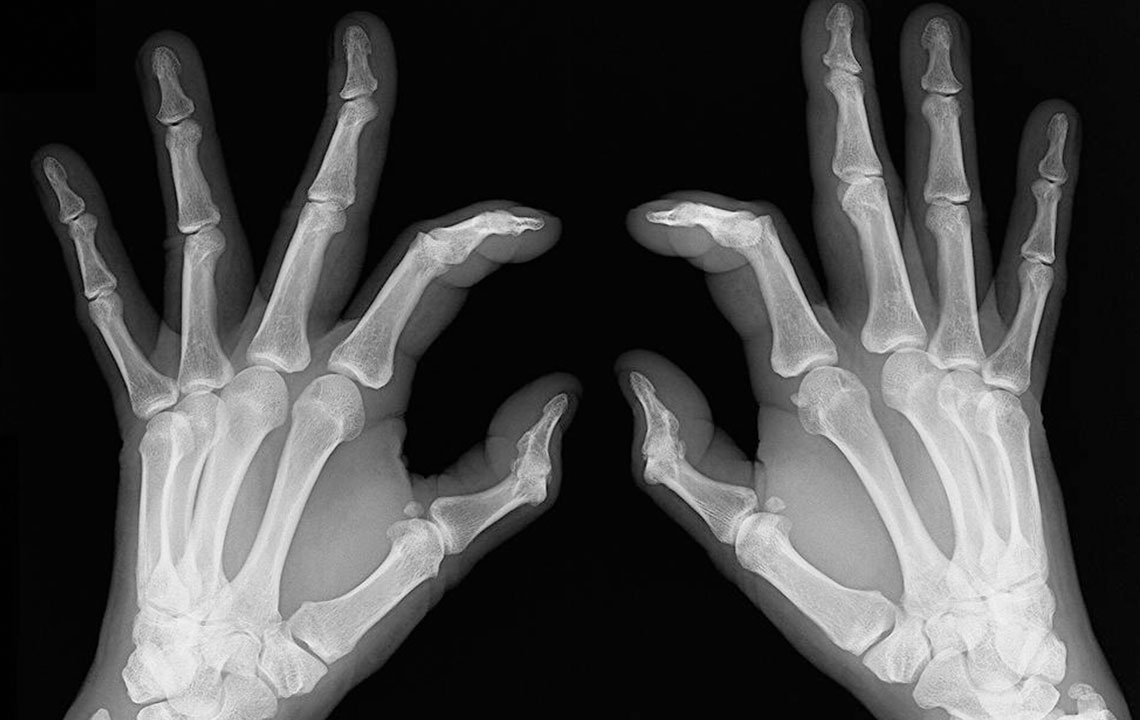

- Bone deformation: Arthritis also attacks the bones and makes them crooked and stiff. Look out for signs of any subtle changes in your joints and test them for pain levels.

Rheumatoid arthritis causes chronic inflammation of joints, which results in joint pains, inflammation and bone deformation. It usually starts slowly with pain in some parts of the body that can come and go in the beginning and then spread within weeks or months. It is better in this day and age to always be aware of your health problems and not to ignore slightest of joint pains.